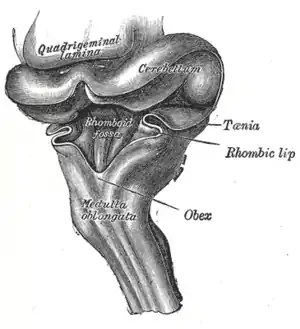

Cerebro posterior de un embrión humano de tres meses-en vista posterior y parcialmente desde el lado izquierdo. La fosa romboidea está en el centro. | ||

La fosa consta de tres partes:[1]

- La parte superior es de forma triangular y está limitada lateralmente por el pedúnculo cerebeloso superior; su ápice, dirigido hacia arriba es continuo con el acueducto cerebral, su base está representada por una línea imaginaria a nivel del límite superior de la fóvea superior.

- La parte intermedia se extiende desde este nivel a las porciones horizontales de las tenías del ventrículo. Es estrecha en la zona superior, donde está limitada lateralmente por el pedúnculo medio, pero se ensancha hacia abajo y se prolonga en los recesos laterales del ventrículo.

- La parte inferior es triangular y su ápice dirigido hacia abajo, llamado el calamus scriptorius, es continuo con el canal central de la parte cerrada de la medula oblongada.